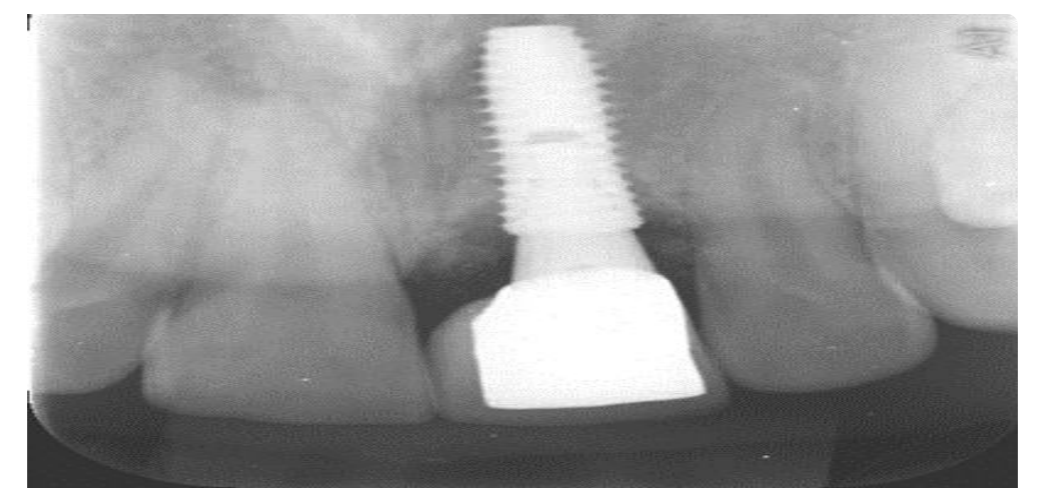

• In cases where an individual tooth is missing, a single implant is employed. This implant serves as a substitute for the tooth’s root, being securely anchored into the jawbone.

• Following a healing period of approximately 3 to 4 months, an abutment is carefully chosen and affixed. Subsequently, a dental crown is placed atop the abutment. This method is an exceptional choice for replacing a single missing tooth, as it circumvents the need to modify adjacent teeth, a common requirement in crown and bridge procedures. The result is a more natural sensation during eating, closely mimicking the feel of a natural tooth.

Here we can see that a single implant is embedded into the bone, and with the aid of an abutment, a crown is securely placed